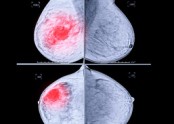

• ■ 정기적으로 유방촬영하는 것이 왜 중요할까요?    ① 아래 환자분은 30대 중반에 검진상 양성 석회화가 있던 분으로 5년 되던 40세에 국가암 검진을 했고, 이때 과거에는 보이지 않던 소견으로 유방촬영 하부 작은 부위에 …